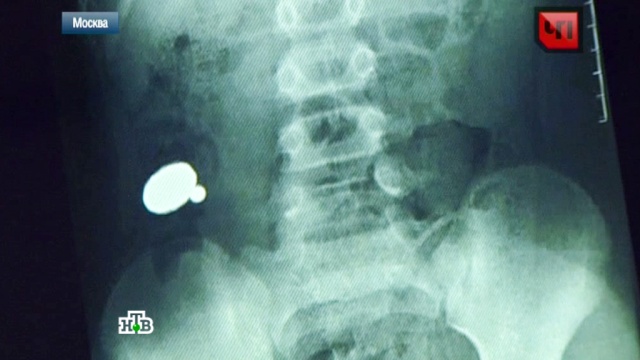

В семье Лаврентьевых из Норильска до сих пор не могут оправиться от горя. Когда у двухлетнего Алеши заболел живот, взрослые подумали, что это отравление. Врачи поставили диагноз «гастрит». А когда ребенок впал в кому, срочно сделали рентген и на снимке увидели, что в желудке малыша с десяток металлических шариков, но было поздно. Алеша умер сразу после операции. После смерти ребенка в Следственном комитете тогда начали проверку. Экспертиза показала, что трагедия произошла именно